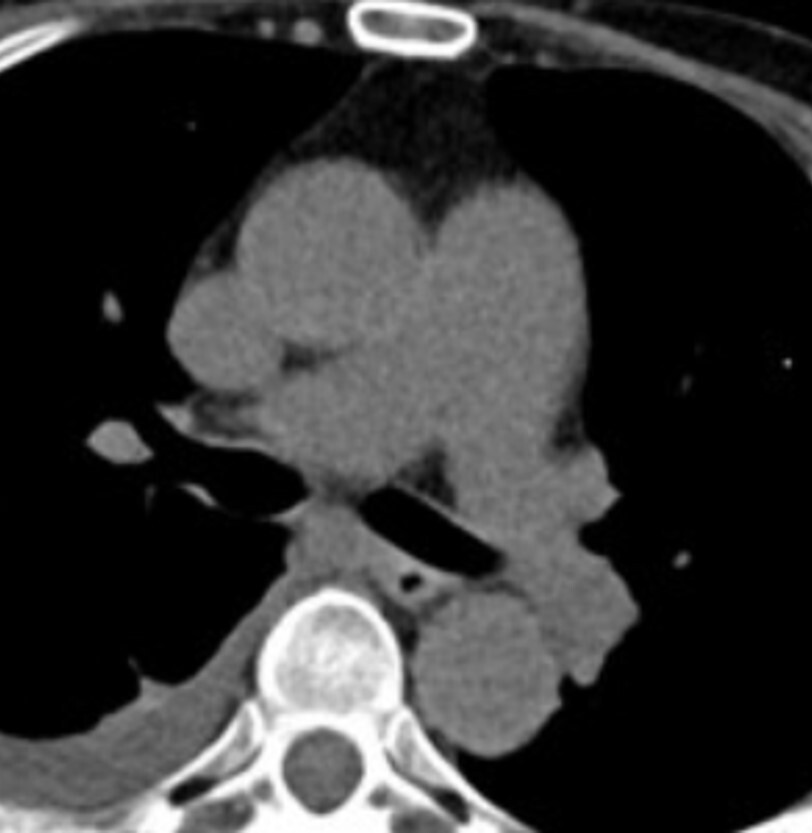

9

Q

What phase of contrast enhancement is seen in the abdomen CT image?

a. Non-contrast

b. Arterial

c. Venous

d. Delayed

A